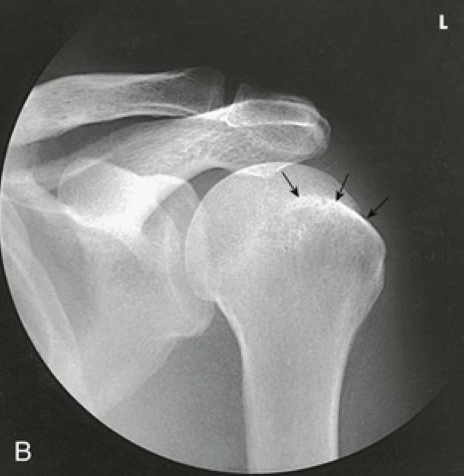

Question

Label the image

Image:

24474d13-c631-43f0-b8a7-2368ffaeab8c (image/jpeg)

Answer

supraspinatus muscle